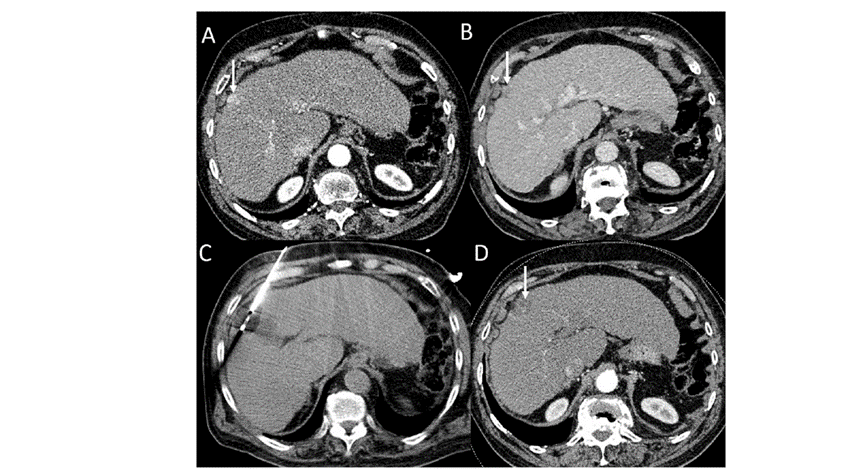

冷冻消融肝包膜下肝细胞癌

(A)动脉期CT图像显示有一个包膜下结节(箭头)。

(B)门静脉期CT图像显示病灶区(箭头)。

(C) 在手术过程中的CT显示一个冷冻探针位于病灶内。

(D)消融后,术后1个月影像CT显示完全消融。